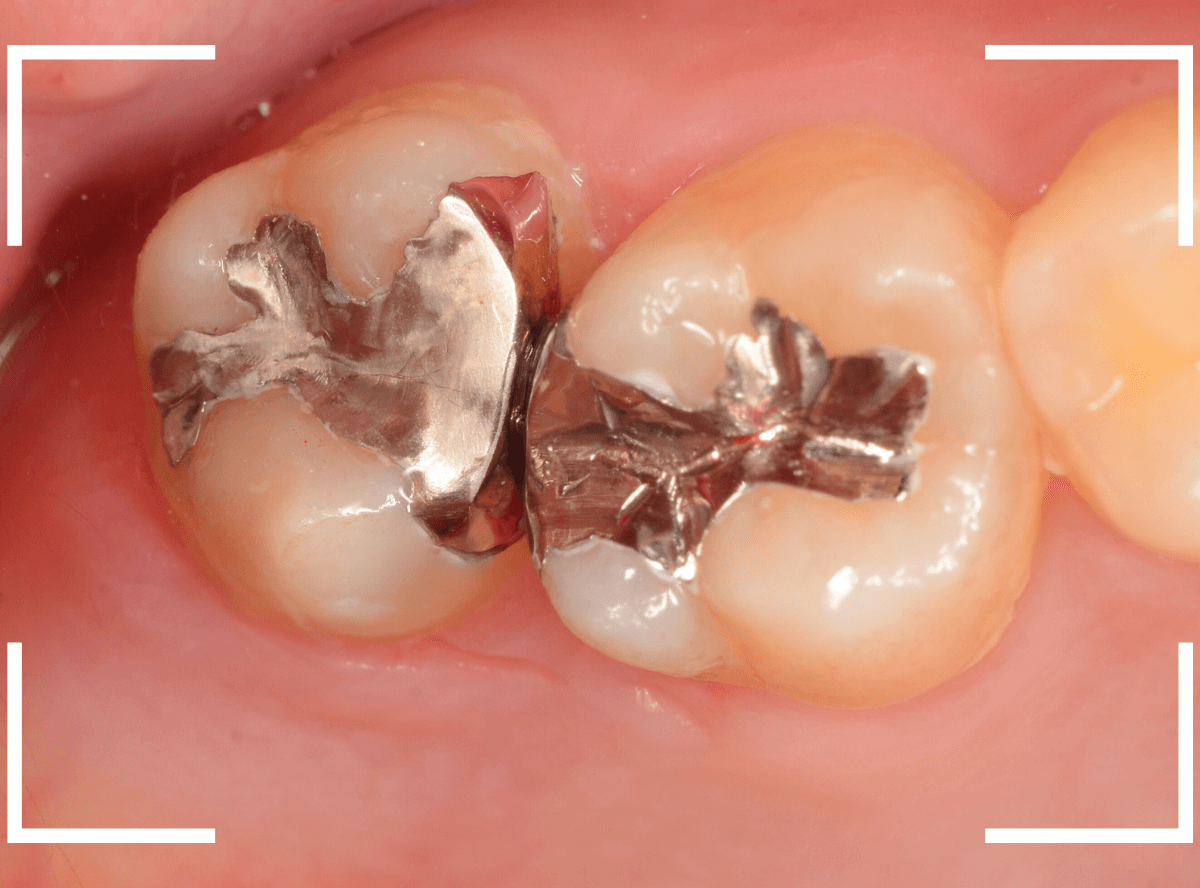

Case.25 レントゲン所見と目視を頼りに、虫歯治療

検査時に〇部、歯と歯の間の小臼歯部に虫歯らしき黒い影があるのが見つかりました。

かなり怪しいですが、メタル・インレーが入ってるので、それが透けている可能性もあります。

レントゲン写真で確認します。

レントゲンでは後ろの大臼歯部の方が虫歯になっているように見え、小臼歯部は問題ないように見えます。

まず大臼歯のインレーを外して、中を調べます。

あれ、インレー直下は虫歯がなさそうです。

レントゲン写真を頼りに、歯を削ると、虫歯が出てきました。

大臼歯の虫歯を削っていくと、手前の小臼歯まで虫歯がつながっていました。

やはり、黒い影は虫歯でした。これは深そうです。

メタル・インレーも外して、虫歯を除去します。

全ての虫歯を除去しました。

レントゲン写真では確認できませんでしたが、手前の小臼歯は深い虫歯でした。

このように、歯と歯の間の虫歯は、深い事が多いです。